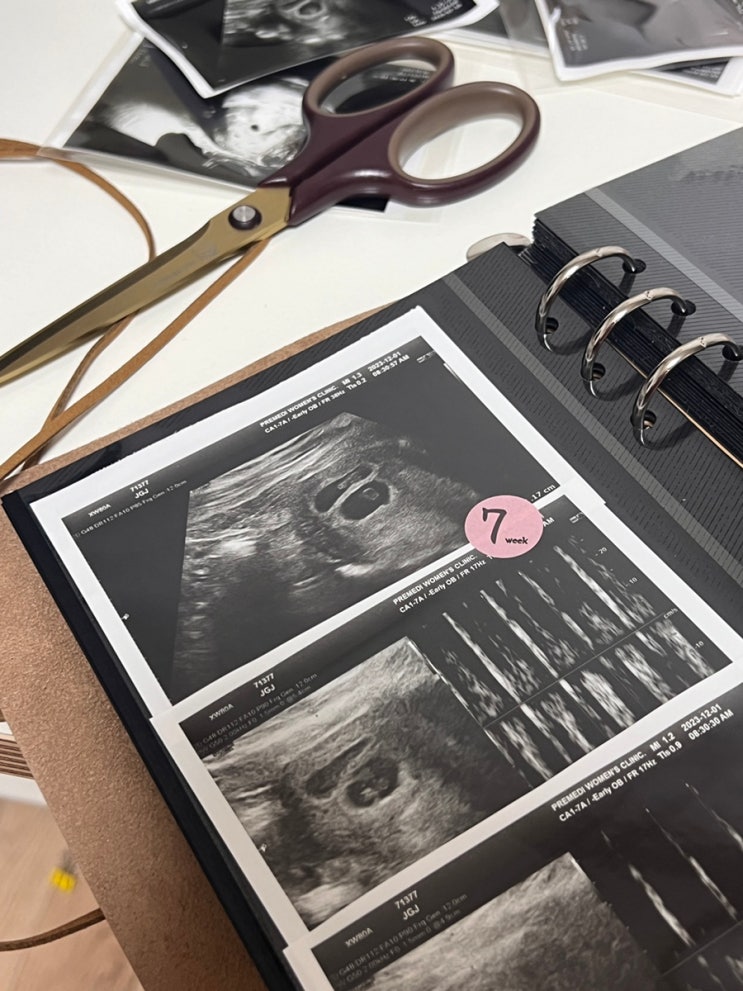

임신8-9주차 별거없는 일상

벌써 임신 9주하고 4일째라니.. 믿을수없이 호다닥 지나가고있댜 아직도 내가 임신이란건 믿기지않고 입덧...